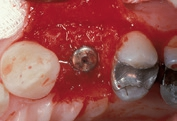

Dieser Patient wurde bereits im Jahr 1991 behandelt. Der Fall zeigt eine der ersten klinischen Anwendungen von Geistlich Bio-Oss Collagen. Aufgrund des intraalveolären Knochendefekts wurde eine Frühimplantation mit gleichzeitiger Augmentation durchgeführt. Die Implantation wurde 6 Wochen nach Extraktion des Prämolars vorgenommen. In der postoperativen Phase erfolgte eine unauffällige Weichgewebeheilung nach Extraktion. Für die Implantatinsertion wurde der Frühimplantationsansatz mit einer Heilungsphase von 6 Wochen gewählt. Die Knochenaugmentation wurde gleichzeitig mit der Implantatinsertion durchgeführt. Das Implantat wurde nach der Lappenpräparation an einer Stelle mit einem schweren Knochendefekt eingesetzt.

Für den Knochenaufbau wurde Geistlich Bio-Oss Collagen in den Defekt appliziert und nach der Augmentation die Eingriffsstelle mit einem Kollagenvlies abgedeckt. Weitere 6 Monate nach dem Eingriff wurde die endgültige Kronenrestauration eingesetzt. Bei der weiteren Nachuntersuchung nach nunmehr 25 Jahren zeigte die Röntgenaufnahme ein stabiles Implantatlager und das klinische Bild bei der Nachkontrolle einen ästhetischen Zahnstatus.